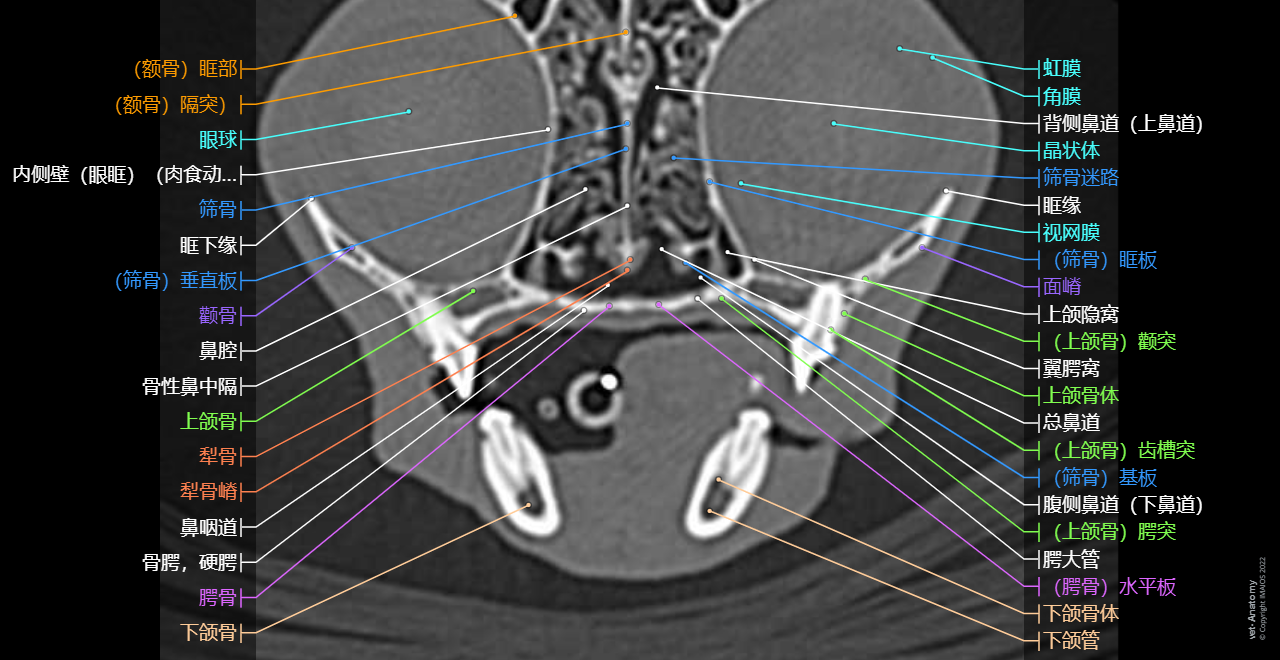

正常猫的头颈部CT解剖

- Antoine MICHEAU, MD , Denis HOA, MD , Susanne AEB Boroffka, PhD - dipl. ECVDI

- 发布日期: 2019年10月11日 | 最新更新 2025年3月18日